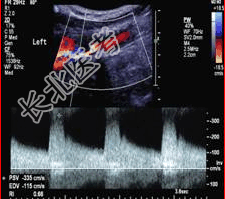

- 简答题2、颅脑CT:未发现明显异常。颈动脉超声检查如下图。根据图像判断病变程度是什么?